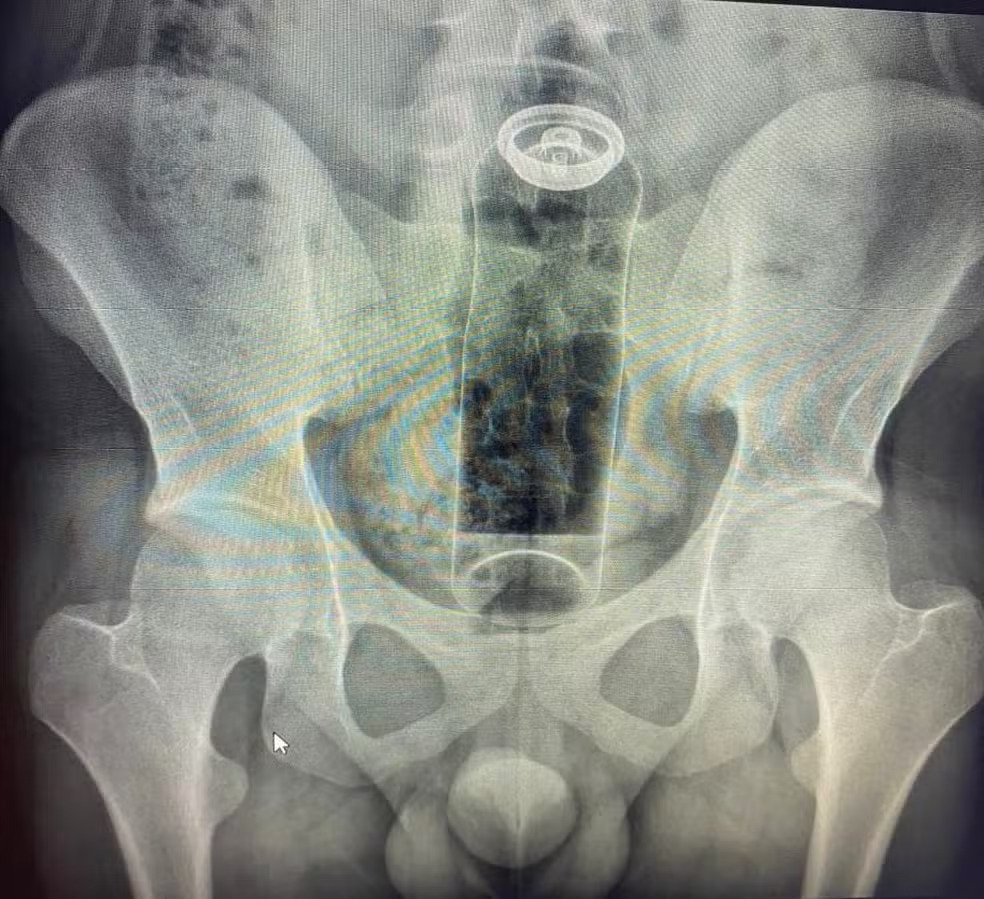

Tag: desodorante preso no reto

Desodorante preso no ânus expõe riscos do uso inadequado no sexo anal

Um caso relatado nas redes sociais pelo cirurgião coloproctologista Daniel Brosco reacendeu o debate sobre como experienciar o prazer anal de forma saudável. No vídeo, o médico conta ter atendido um paciente de 19 anos que foi internado ao introduzir um desodorante no ânus durante uma brincadeira sexual. Como resultado, o produto subiu para o reto e o homem não conseguiu […]